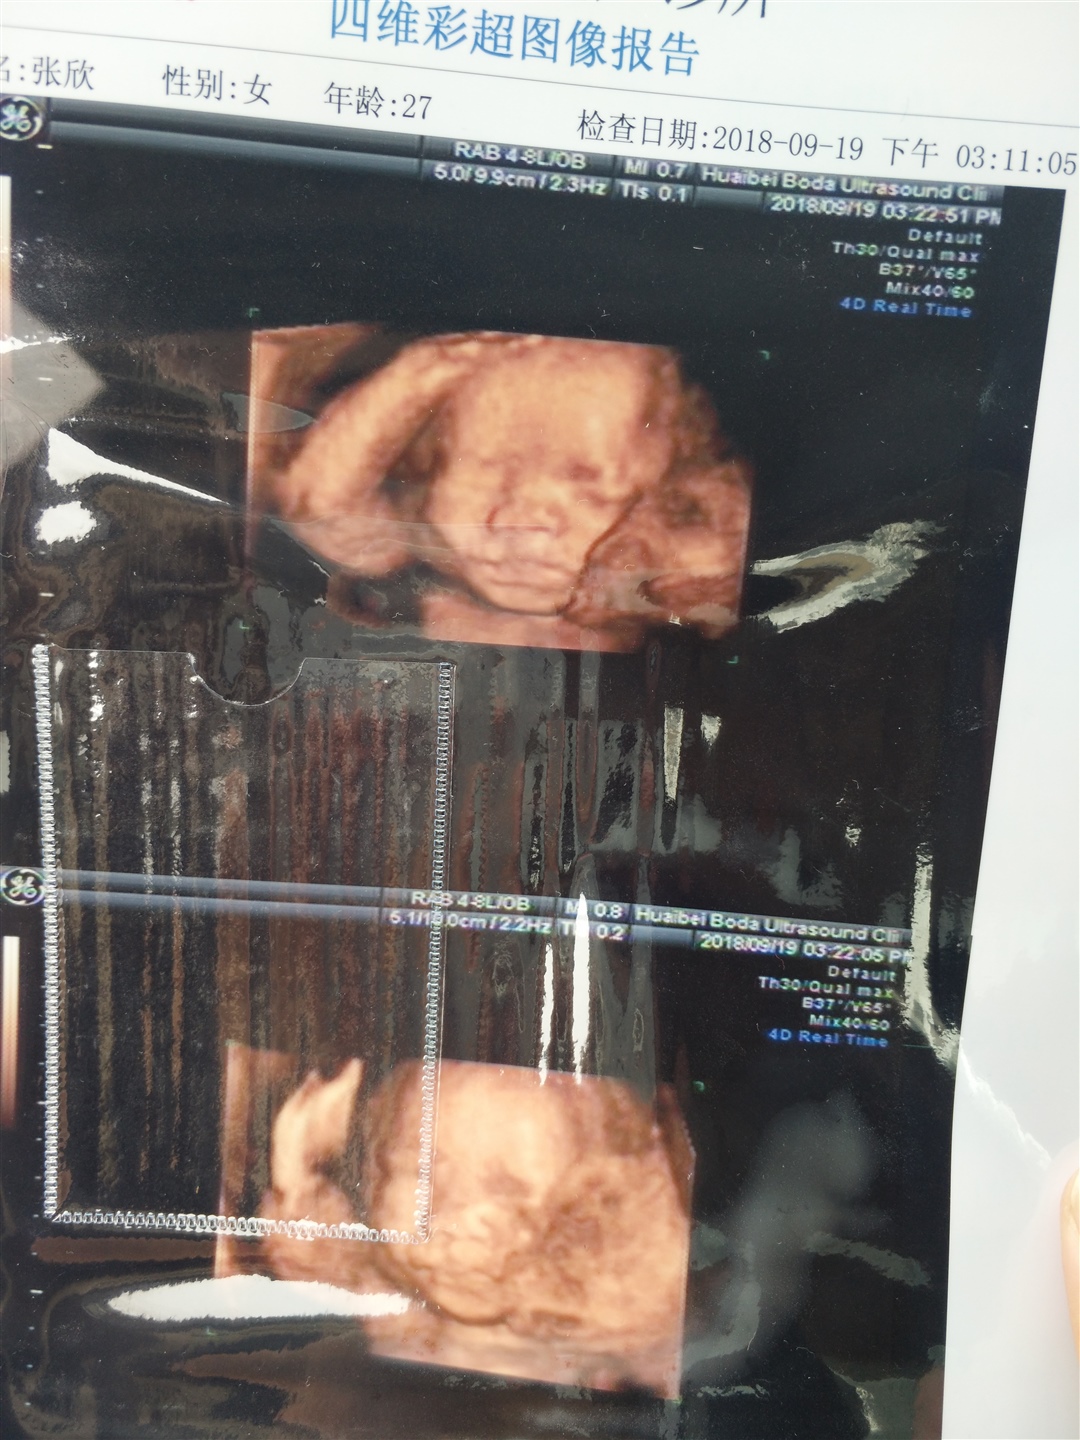

孕9周+6天

孕7周+5天